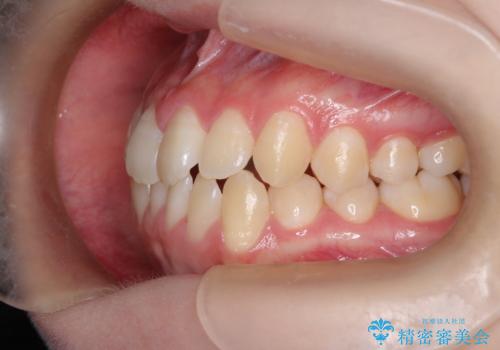

右上小臼歯の捻転を改善|インビザラインと部分ワイヤー矯正のコンビネーション治療

- 右上の小臼歯が大きくねじれており、噛み合わせや見た目に影響を与えている状態でした。診察の結果、インビザライン単独では十分な回転が得られにくいと判断。そのため、基本的な歯列の移動はインビザラインで行いながら、部分的にワイヤー矯正を併用するコンビネーション治療を計画しました。

まず、インビザラインで歯列全体を整えながら、スペースを確保しました。その後、部分ワイヤーを装着し、右上小臼歯の捻転を効率よく改善。ワイヤーの力を活用することで、より確実に歯の向きを整えることができました。治療後は、「しっかり噛めるようになり、見た目も自然になった」と患者様にもご満足いただきました。